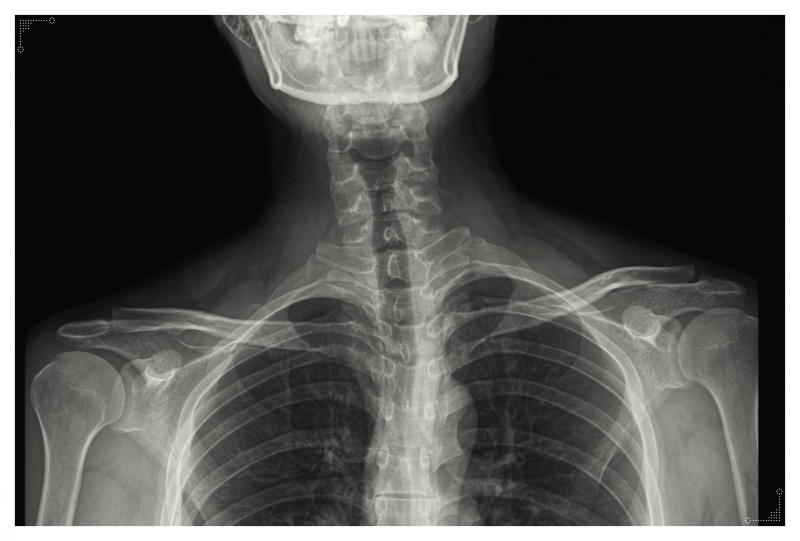

Q. 목·어깨·척추·골반을 함께 보는 이유

말씀드렸듯이 어깨 통증은 어깨 하나만의 문제가 아닌 경우가 많습니다.

목이 굽으면 어깨가 말리고,

어깨가 말리면 등의 긴장이 쌓입니다.

골반이 틀어지면 상체 균형이 무너지면서

어깨 근육이 더 긴장하게 되죠.

즉, 한 부위에서 나타나는 것처럼 보여도

실제로는 전신의 균형이 함께 영향을 주는 구조입니다.

그래서 치료 접근 역시

어깨만 보는 것이 아니라 전신을 바로 잡는 방식으로 이어져야 합니다.